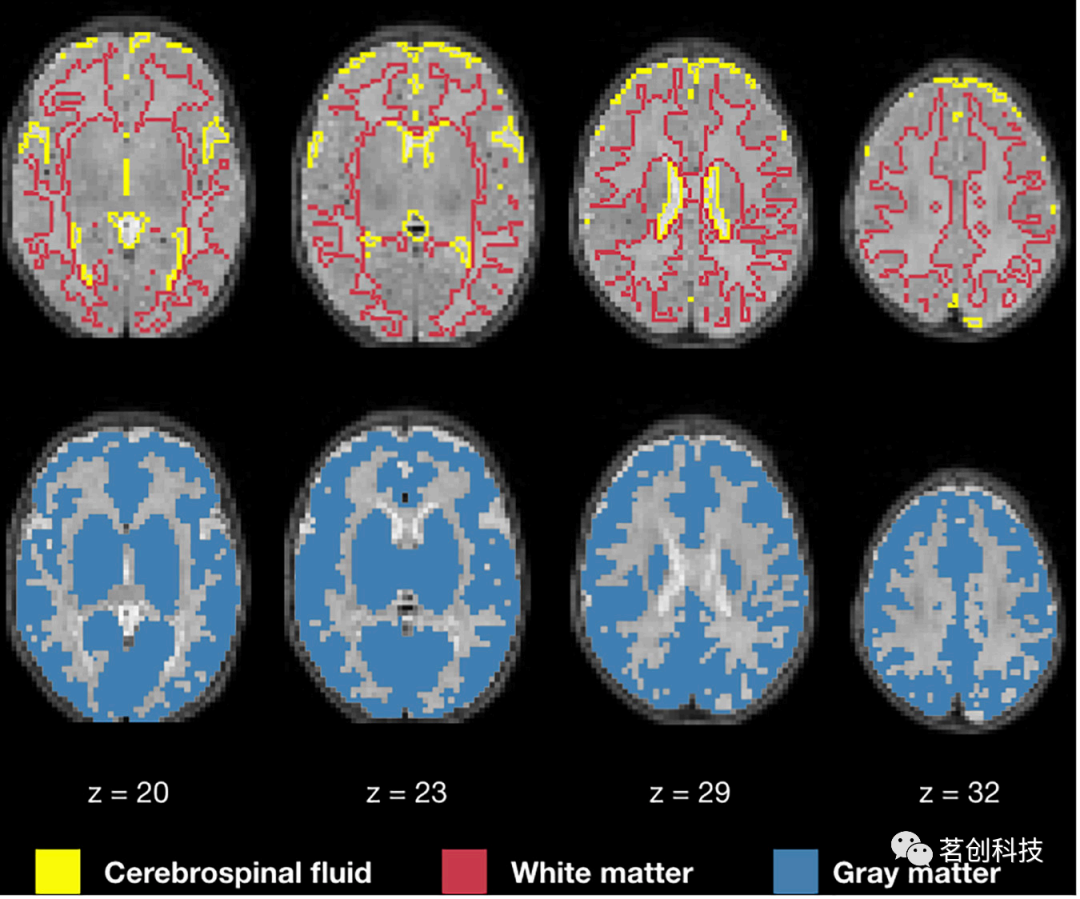

图6显示了NeoRS从Mantis组织概率图中创建的1mm各向同性二元掩膜。输出包含三个不同的二元文件,分别对应白质、SCF和GM。图7展示了用于混淆回归过程的3mm各向同性掩膜。

图7.白质、脑脊液和灰质掩膜用于混淆回归。